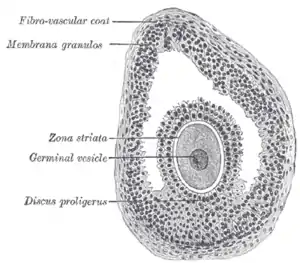

In the primordial ovarian follicle, and later in follicle development (folliculogenesis), granulosa cells advance to form a multilayered cumulus oophorus surrounding the oocyte in the preovulatory or antral (or Graafian) follicle.

Cumulus cells surround the oocyte. They provide nutrients to the oocyte and influence the development of the oocyte in a paracrine fashion. Mural granulosa cells line the follicular wall and surround the fluid-filled antrum. The oocyte secretes factors that determine the functional differences between CCs and MGGs. CCs primarily support growth and development of the oocyte whereas MGCs primarily serve an endocrine function and support the growth of the follicle. Cumulus cells aid in oocyte development and show higher expression of SLC38A3, a transporter for amino acids, and Aldoa, Eno1, Ldh1, Pfkp, Pkm2, and Tpi1, enzymes responsible for glycolysis.[7] MGCs are more steroidogenically active and have higher levels of mRNA expression of steroidogenic enzymes such as cytochrome P450.[8] MGCs produce an increasing amount of estrogen which leads to the LH surge.[9] Following the LH surge, cumulus cells undergo cumulus expansion, in which they proliferate at a ten-fold higher rate than MGCs in response to FSH.[10] During expansion CCs also produce a mucified matrix required for ovulation.[11]

Additional images